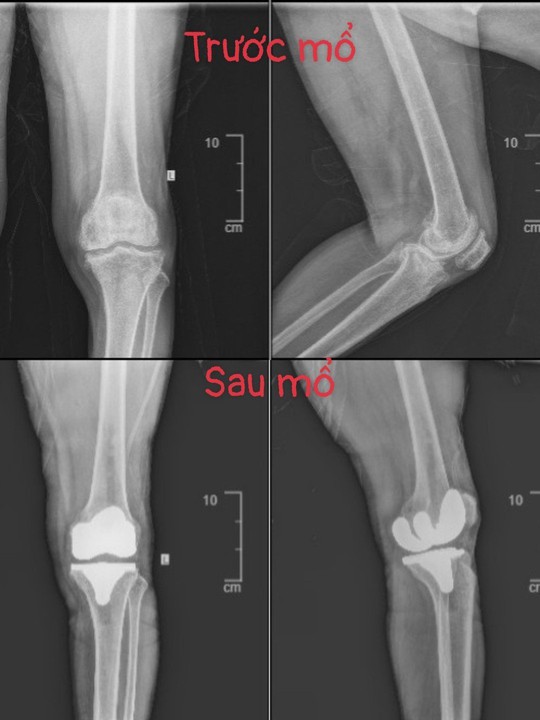

Đối với bệnh nhân L.V.T, kết quả chụp X-quang gối cho thấy bệnh nhân bị thoái hóa khớp gối nặng hai bên, trong đó khớp gối bên phải bị thoái hóa mức độ nặng hơn. Kèm theo bệnh nhân có bệnh lý tăng huyết áp và phương án điều trị phù hợp là phẫu thuật thay toàn bộ khớp gối phải.

Hình ảnh khớp gối được thay qua hai cuộc phẫu thuật. Ảnh: BVCC

Bác sĩ Khanh cho biết đây là một trường hợp phẫu thuật khó vì bệnh nhân đã bị đau và biến dạng gối nhiều năm, toàn bộ bề mặt khớp gối phải đã bị hư hỏng nặng.

Ca phẫu thuật diễn ra trong 2 giờ và thực hiện thành công. Sau phẫu thuật, tình trạng sức khỏe bệnh nhân ổn định, biến dạng chân đã được khắc phục, không còn đau gối phải. Bệnh nhân đã tập đi lại nhẹ nhàng với chương trình phục hồi chức năng sau mổ, thời gian sau đó đi chịu lực hoàn toàn nhờ gối phải.

Một tháng sau, bệnh nhân được phẫu thuật thay khớp gối trái. Qua hai cuộc phẫu thuật, chân được chỉnh thẳng trục, bệnh nhân đã đi cân bằng được hai bên, đi thẳng lưng, gối không còn đau.